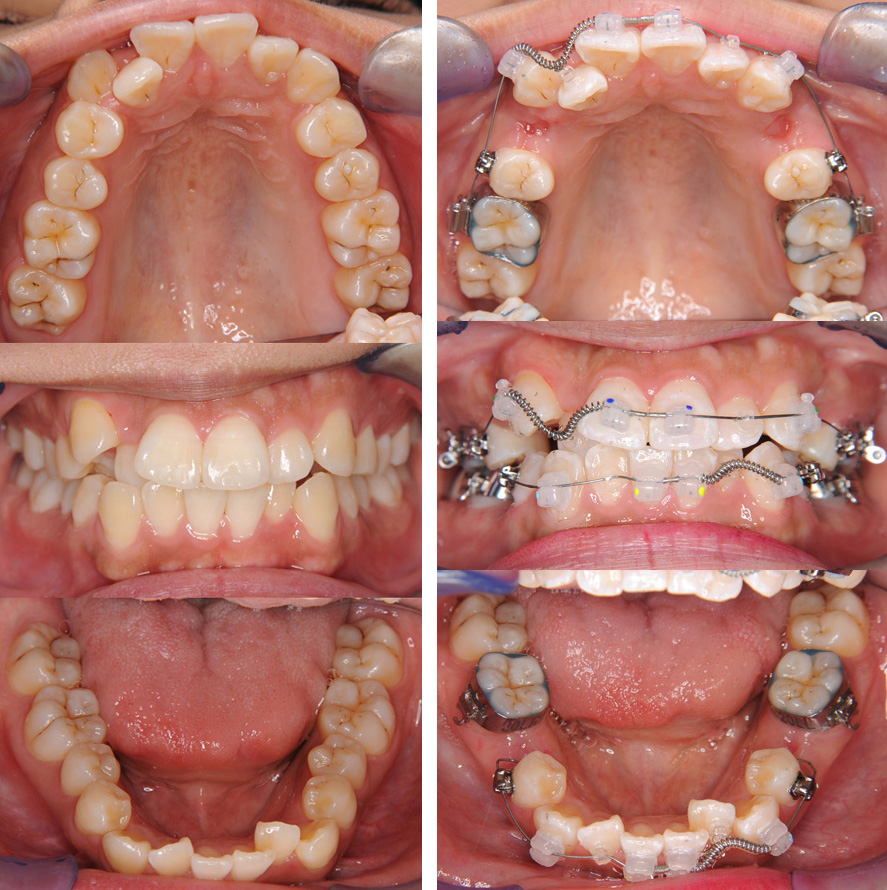

下左:歯を抜いたすき間が閉じ微調整中(装置装着後2年5か月)

下右:治療終了時(装置装着後2年6か月)

-治療に関する詳細-(1)主訴(患者が一番気になること):歯がガタガタしている.(2)診断名:叢生(歯並びのガタガタ).(3)治療開始時年齢:22歳.(4)使用した装置:マルチブラケット装置.(5)抜歯部位:上顎左右手前の小さい奥歯(第1小臼歯),下顎左右2番目の小さい奥歯(第2小臼歯).(6)治療期間・回数:2年6か月(マルチブラケットで歯を動かした期間〈治療回数24回・難易度により回数は増えます〉・その後、保定(歯を安定させる)治療〈治療回数8回〉に移行・「矯正装置について」ページ下段参照).(7)費用の目安:1,012,000円/税込 (920,000円/税別)

2024年の成人治療費用・保定治療までの総額/検査・診断料別途.(8)リスク・副作用など:a.矯正力により痛みが出ることがあります. b.矯正装置によりむし歯のリスクが高まります.c.装置の脱離などにより臨時の受診が必要となることがあります.d.治療により歯の根が短くなることがあります.e.まれに歯と骨が癒着し動かないことがあります.f.治療後歯並びは生涯変化します.g.舌の癖・顎骨の成長・治療前の難易度などにより理想的咬み合わせと異なる仕上がりとなることがあります.h.「転医」により治療に時間を要したり治療方針が変更となことがあります.さらに詳しい情報は「矯正治療のリスク・副作用」ページを参照ください..